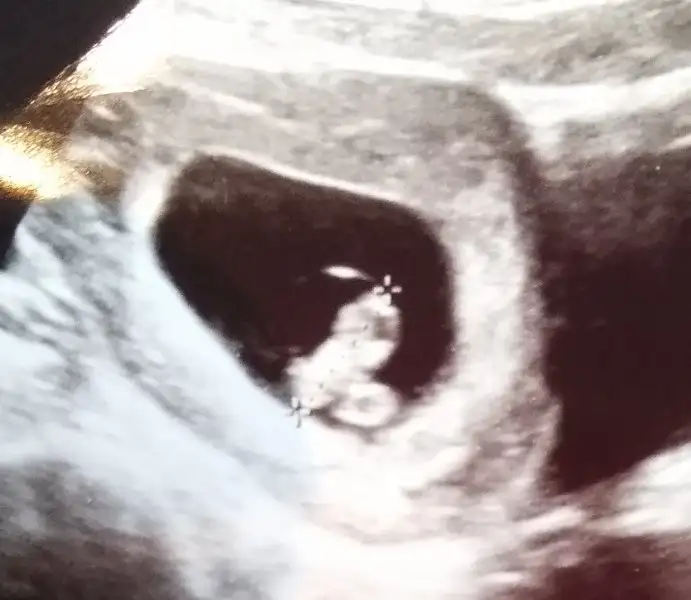

Zor süreçlerden geçtim. 2 yıl bebeğim olmadı, tüp bebek tedavisi gördüm ilk bebeğimi kaybettim 14 haftalıkken. Kan pıhtılaşmam varmış. İnşallah bu sefer sağ salim yavrumu kucağıma alırım.

Bugünkü resmini paylaşayım sizinle, içinizden gelen güzel duaları yavruma okursanız çok sevinirim. Rabbim hepimizin yardımcısı olsun inşallah.